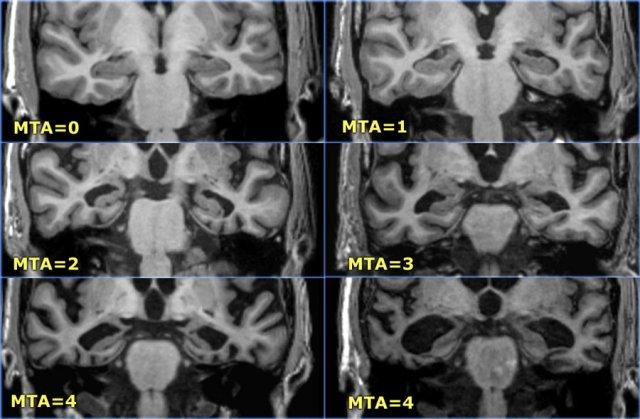

Điểm MTA cần được đánh giá trên chuỗi xung T1W mặt phẳng coronal tại một vị trí lát cắt nhất quán.

Chọn lát cắt qua thân hồi hải mã, ở mức cầu não trước.

Điểm số được tính dựa trên đánh giá trực quan chiều rộng của khe mạch mạc, chiều rộng của sừng thái dương và chiều cao của cấu trúc hồi hải mã.

- Điểm 0: Không có teo não

- Điểm 1: Chỉ giãn rộng khe mạch mạc

- Điểm 2: Kèm theo giãn rộng sừng thái dương của não thất bên

- Điểm 3: Mất thể tích hồi hải mã mức độ vừa (giảm chiều cao)

- Điểm 4: Mất thể tích hồi hải mã mức độ nặng

< 75 tuổi: Điểm từ 2 trở lên là bất thường.

> 75 tuổi: Điểm từ 3 trở lên là bất thường.

Tại đây bạn có thể cuộn qua các hình ảnh minh họa điểm MTA từ 0 đến 4.